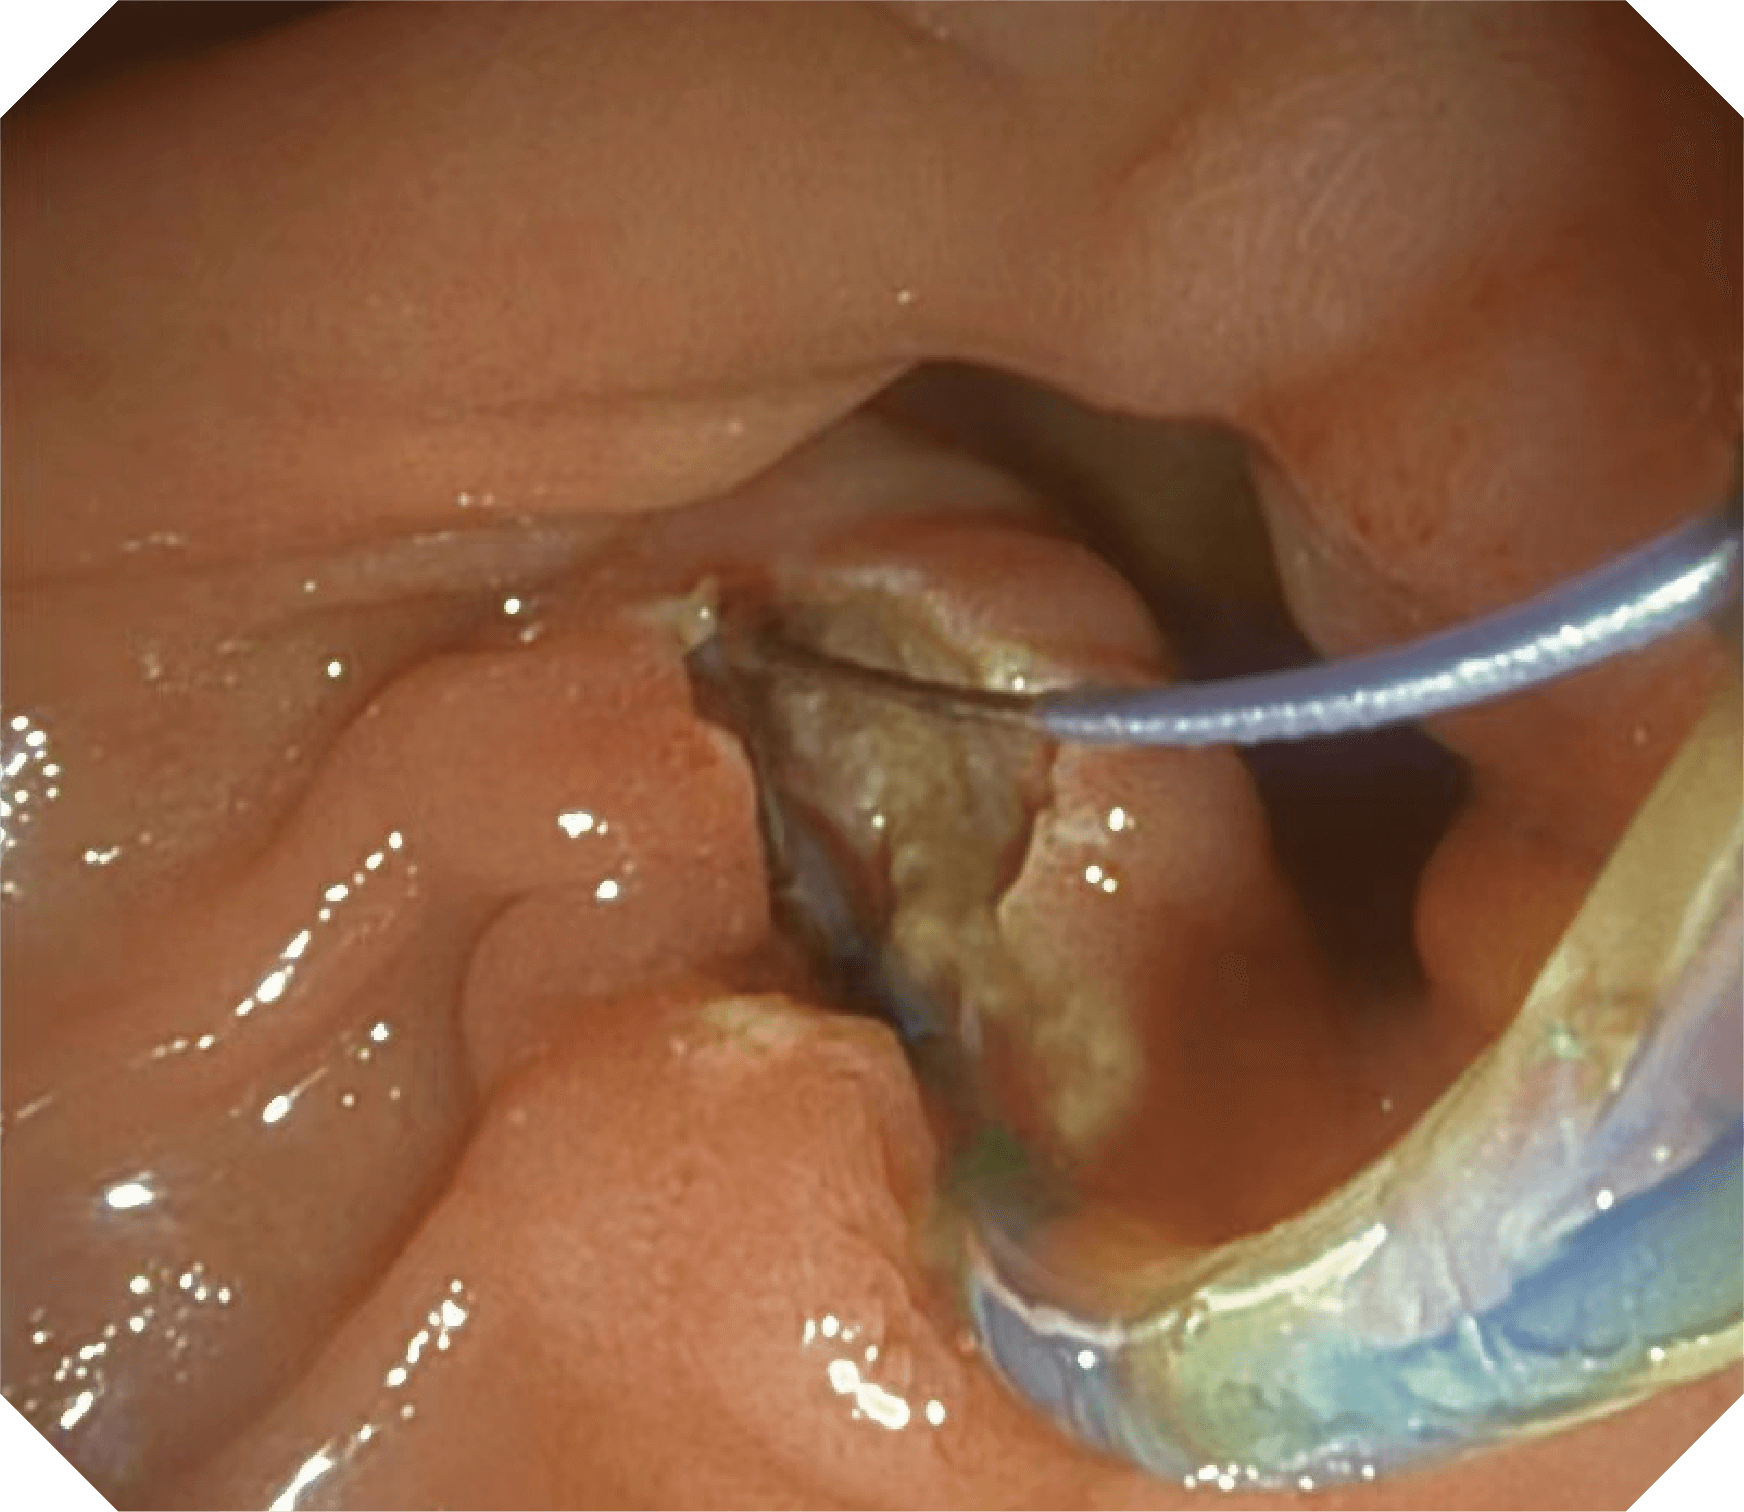

4.2mm大钳道,器械交换更顺畅

优异的手术器械抬举性